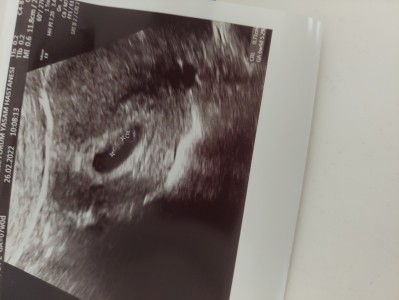

Burda 7 haftalık  çok erken biliyorum ama içinize ne doğuyor

Yok canım daha kolu bacağı yeni çıkıyor yavrunun

Kesenin şekline göre bazen tahmin ediliyor

Kiz diyimde net deilim :)